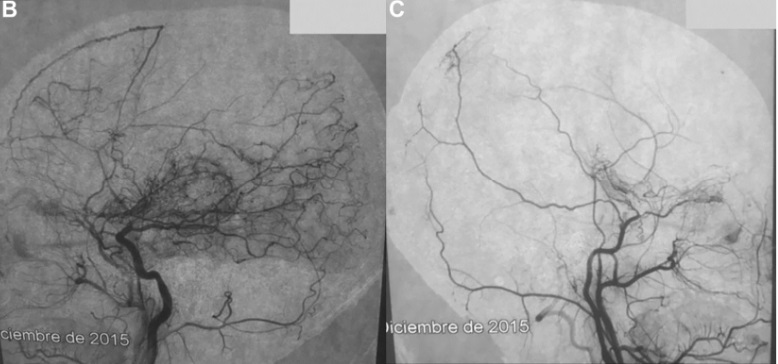

因此,该患者在左颞浅动脉和左大脑中动脉之间接受了两次直接搭桥手术,由主刀川岛明次教授完成手术(图2)。

▼图2术后CTA的3D重建显示开颅手术大小,以及在左侧颞浅动脉和左侧大脑中动脉之间进行的两次搭桥血管重建。